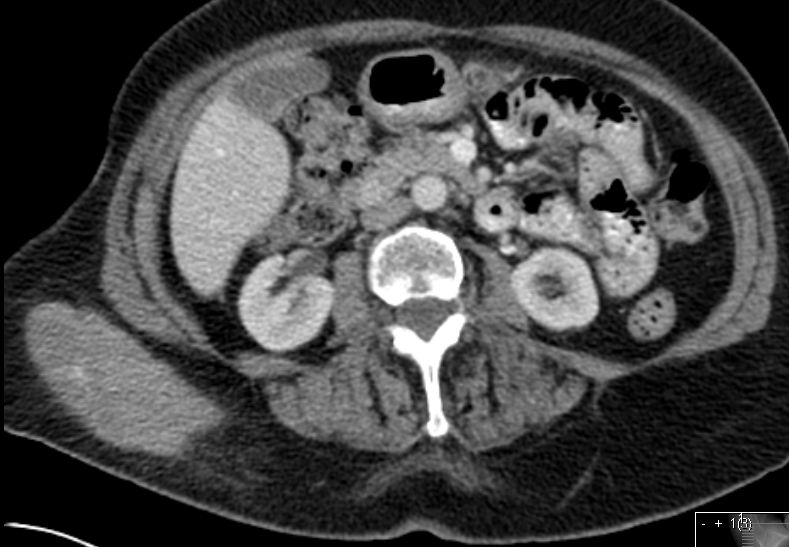

extranodales MZoL |

Epidemiologie |

Zusammenhang mit Autoimmunerkrankungen und chronischen Infektionen (2): | ||||||||||||||||||||||||||||||||||||

Campylobacter jejuni | Dünndarm | Chlamydia psittaci | Augenanhangsgebilde | Borrelia burgdorferi | Haut | Hepatitis C Virus | MZoL der Milz | |||||||||||||||||||||||||||||